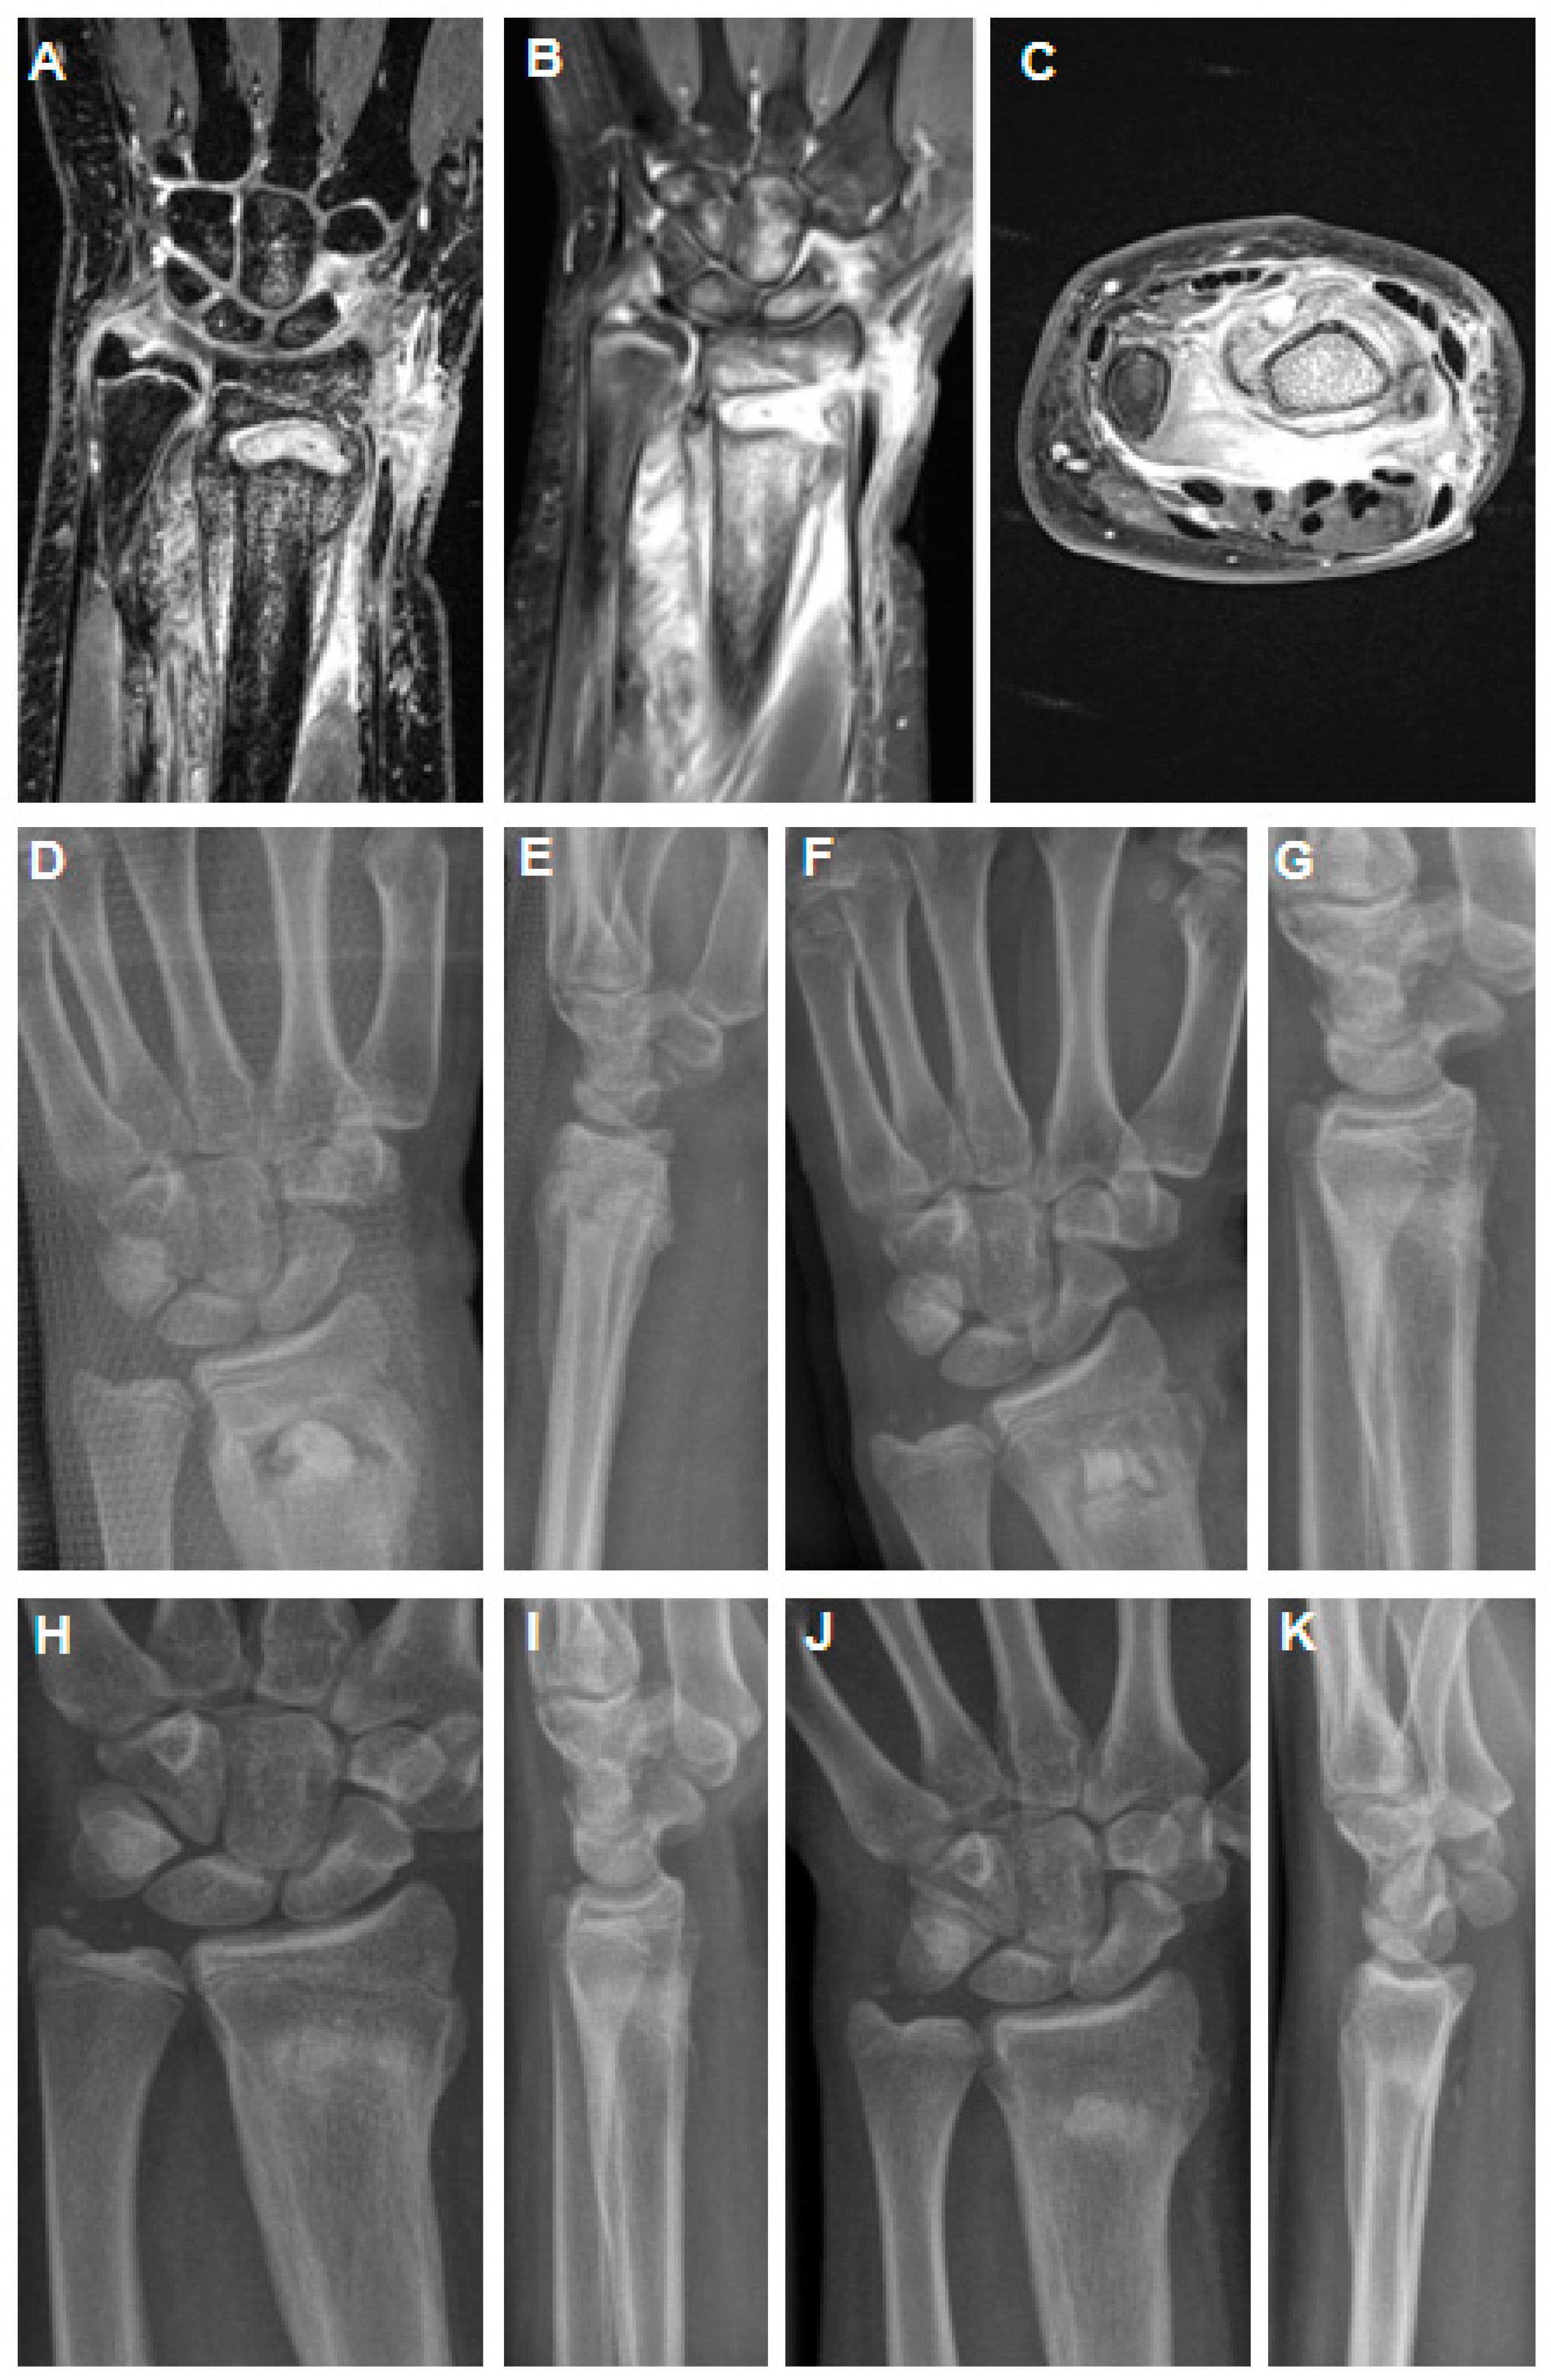

2.1. Case 1

2.2. Case 2